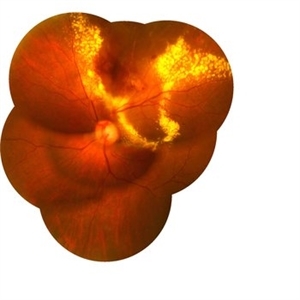

Coats' Disease

Fundus image of Right eye of a 12-year-old boy presented with dimness of vision for 6 months. Image showed lot exudation along the telengiectatic vessels at periphery. Cystoid macular edema also noted.

Photographer: Krishnendu Nandi, Netralayam Eye Hospital, Kolkata, India

Condition/keywords: Coats' disease, retinal telangiectasia